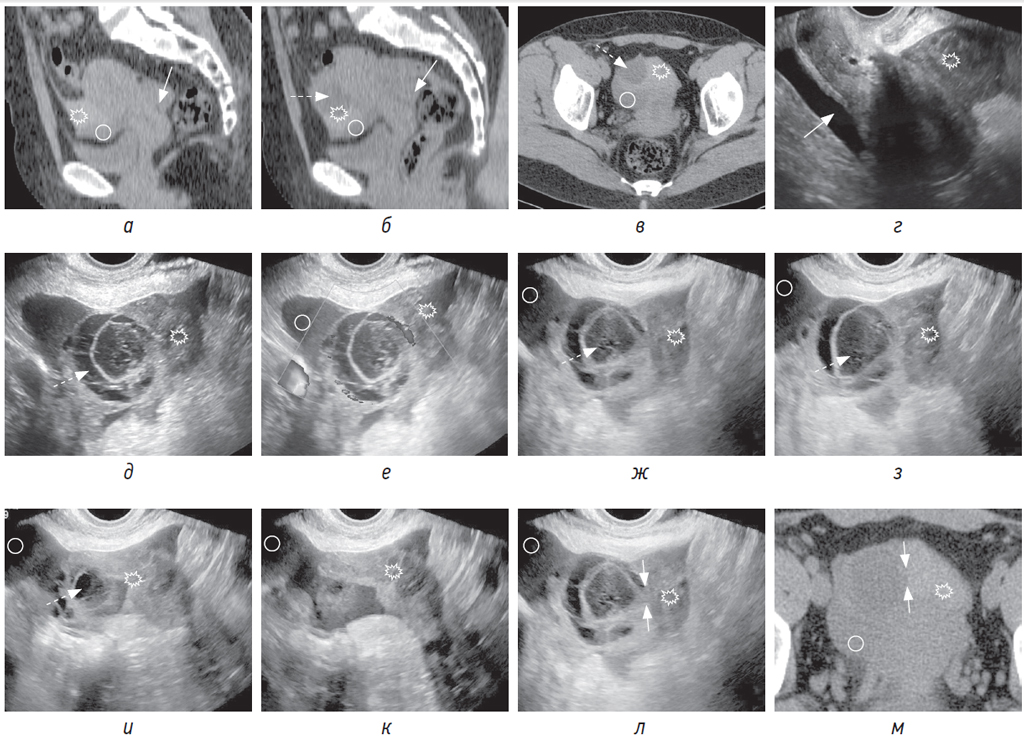

Рис. 1. Пациентка 33 лет поступила с резкой болью в правой подвздошной области. В связи с подозрением на аппендицит была проведена нативная КТ. На КТ-томограммах в сагиттальной (а, б) и аксиальной (в) плоскостях в маточно-пузырном пространстве визуализируется жидкая кровь (круг) и сгусток (звездочка), прилежащий к кистозному образованию (пунктирная стрелка) в правом яичнике; в маточно-прямокишечном пространстве — жидкая кровь (стрелка). При трансвагинальном УЗИ по длинной оси матки (г) визуализируется жидкая кровь в маточно-прямокишечном пространстве (стрелка) и сгусток в маточно-пузырном пространстве (звездочка). На серии трансвагинальных сонограмм в В-режиме (д–к) и с использованием ЦДК (е) в правом яичнике определяется кистозное образование (пунктирная стрелка) с толстой и гиперваскулярной стенкой, с геморрагическим содержимым, с наличием параовариально эхогенной крови (круг) и сгустков крови (звездочка). Предполагаемое место разрыва показано между стрелками на сонограмме (л) и соответствующей нативной КТ-томограмме в аксиальной плоскости (м)

При КТ и УЗИ важно определить локализацию сгустка, которая, как правило, указывает на источник кровотечения. Так называемый «сторожевой сгусток» тесно прилежит к травмированному яичнику непосредственно в месте разрыва (рис. 1, а–в, д–м; 2, д–е; 3, г–е). В случае продолжающегося кровотечения сгусток может быть больших размеров и охватывать яичник на большом протяжении, что затруднит локализацию места предполагаемого разрыва в яичнике.

Ультразвуковая картина кистозного образования в яичнике зачастую разнообразна. Кистозное образование иногда бывает трудно определить из-за частичного или полного спадения полости либо из-за большого количества прилежащих тромботических масс (рис. 2, г–е) [9]. Кроме того, выявление геморрагической кисты значительно затрудняет полиморфизм сонографической картины: 1) мелкосетчатое и среднесетчатое строение средней эхогенности, в 2/3 случаев эти структуры занимают всю или большую часть кисты (рис. 1, д–з); 2) однородное содержимое в сочетании с множественными или единичными, тонкими, полными или неполными, неправильной формы перегородками; 3) в полости кисты сгустки крови в виде включений преимущественно высокой эхогенности, имеющие неправильную форму и пристеночную локализацию (рис. 3, г) [10].

Рис. 3. Пациентка 27 лет поступила с болью в области малого таза. При трансвагинальном УЗИ (а, б) в левом яичнике определяется спавшаяся полость (а, пунктирная стрелка) неправильной формы с сомкнутым местом разрыва (стрелка), во время исследования полость (б, пунктирная стрелка) увеличилась в размерах за счет кровотечения и увеличилось количество несвернувшейся эхогенной крови (круг) в малом тазу. Трансвагинальная (в) и трансабдоминальная (г) сонограммы: эхогенная кровь в позадиматочном пространстве (круг). Увеличенный левый яичник с наличием полости с геморрагическим содержимым и сгустком, свисающим от места разрыва (г, уступ со стрелкой). На трансвагинальных (д, е) сонограммах: эхогенная кровь в позадиматочном пространстве (круг), увеличенный левый яичник с наличием полости с геморрагическим содержимым (пунктирная стрелка) и сгусток, начинающийся от места разрыва яичника (уступ со стрелкой)

Самой частой причиной разрыва яичника с гемоперитонеумом служит киста желтого тела, для которой при УЗИ характерна толстая стенка с зубчатыми краями. Применение цветового допплеровского картирования (ЦДК) существенно помогает не только в выявлении кисты на фоне тромботических масс, но и в дифференцировке кисты желтого тела от других образований на основании гиперваскуляризации по периферии и отсутствия цветовых сигналов во внутренних перегородках и структурах, представляющих собой организованные сгустки крови и нити фибрина (рис. 1, е; рис. 2, е) [10]. При трансабдоминальном УЗИ выявить спавшуюся кистозную полость практически невозможно, но при трансвагинальном/трансректальном исследовании допплеровские методики могут помочь в ее идентификации (рис. 3, а, б, г–е).

Место разрыва при УЗИ можно предположить на основании следующих признаков:

1) при крупных сгустках, окружающих травмированный яичник, из кистозной полости в параовариальное пространство распространяется ткань, изоэхогенная тромботическим массам; на этом уровне в месте предполагаемого разрыва определяется нарушение целостности капсулы яичника (рис. 1, л, м);

2) при минимально выраженном тромбозе непосредственно к месту предполагаемого разрыва прилежит сгусток, хорошо визуализируемый на фоне жидкой крови (рис. 3, б, г–е).

При КТ кистозное образование имеет различную плотность: 1) низкая плотность в центральной области и высокая плотность по периферии; 2) смешанная плотность в центральной области и высокая плотность по периферии; 3) высокая плотность в центральной области и по периферии [8].

По данным литературы, характеристика стенок кистозного образования возможна на постконтрастных КТ-изображениях. Как правило, это накапливающая контрастное вещество толстая (киста желтого тела) или тонкая (фолликулярная киста) стенка. Предполагаемое место разрыва может определяться в виде прерывистости или неровности контура стенки. На постконтрастном изображении можно выявить активную экстравазацию в месте разрыва кисты [1, 7, 8]. Кроме того, на фоне массивных тромботических масс в полости малого таза только на постконтрастных изображениях по усиливающейся стенке можно определить спавшуюся полость кистозного образования. Исходя из представленных литературных данных и нашего личного опыта, мы рекомендуем врачам-специалистам КТ обращать особое внимание на наличие этих изменений, поскольку именно данные симптомы свидетельствуют о разрыве кисты яичника и позволяют обосновать гинекологическую природу острой боли в животе.